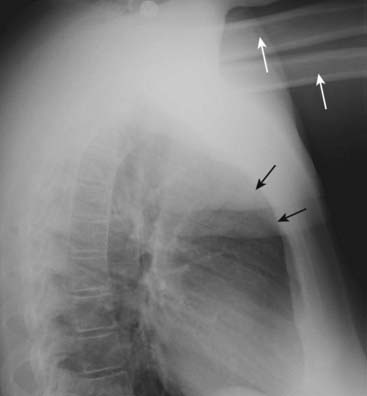

Figure 2-5 Arms obscure retrosternal clear space.

In this example, the patient was not able to hold her arms over her head for the lateral chest examination, as patients are instructed to do in order to eliminate the shadows of the arms from overlapping the lateral chest. The humeri are clearly visible (solid white arrows) so even though the soft tissue of the patient’s arms appears to fill in the retrosternal clear space (solid black arrows), this should not be mistaken for an abnormality such as anterior mediastinal adenopathy (see Fig. 2-4).